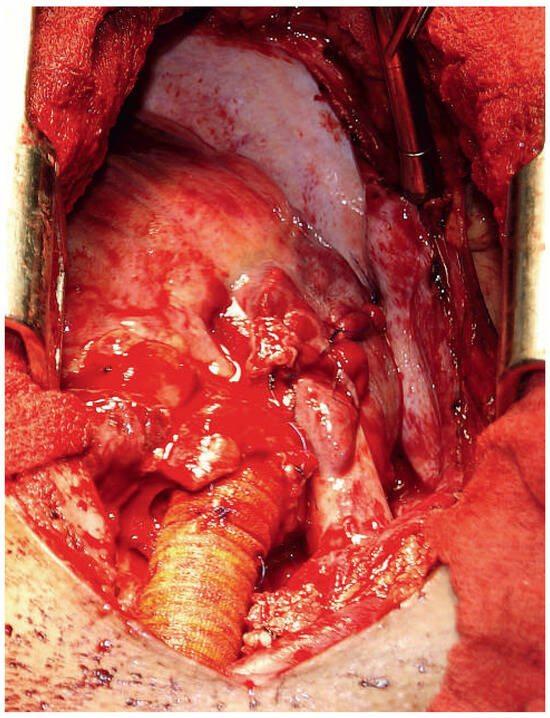

Surviving Acute Traumatic Transection of the Ascending Aorta and Proximal Aortic Arch

We report a 22-year-old male patient who survived clinically unapparent acute traumatic transection of the distal ascending aorta and the proximal aortic arch. Two months after the incident, the patient presented with hoarseness, respiratory distress and severe venous congestion of the upper part [...] Read more.

We report a 22-year-old male patient who survived clinically unapparent acute traumatic transection of the distal ascending aorta and the proximal aortic arch. Two months after the incident, the patient presented with hoarseness, respiratory distress and severe venous congestion of the upper part of the body. Echocardiography demonstrated a huge mediastinal tumour, dilated right heart chambers as well as pericardial tamponade. In the computed tomography (CT), scan rupture of the distal ascending aorta and the proximal aortic arch was found. The preserved adventitial layer, preventing immediate death from exsanguination or pericardial tamponade, distended over time forming a false aneurysm with a diameter of 9 cm, with its main part being located to the left of the trachea. Systolo-diastolic motion of the thin-walled false aneurysm led to the typical pulse-synchronous horizontal motion of the thyroid cartilage and the trachea, described as the Cardarelli sign. As a result of systolic expansion and diastolic shrinking of this huge false aneurysm, the arterial blood pressure curve of the patient perfectly imitated the blood pressure curve seen only with a properly timed intra-aortic balloon pump. In addition, the systolic blood pressure repeatedly compressed the main pulmonary trunk, which crossed the bottom of the false aneurysm, consecutively leading to clinically apparent right heart failure, serous pericardial effusion and pericardial tamponade. The patient successfully underwent ascending aortic and proximal aortic arch replacement using deep hypothermia, circulatory arrest and selective antegrade cerebral perfusion. Full article